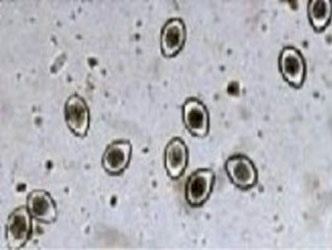

The Coccidia is also known in its initial state as an Oocysts (pronounced o'o-sists), which can easily be visualized as a little “o” inside of a big “O” as seen through the microscopic picture below. Coccidia are spread through fecal matter. Such infected fecal matter is easily passed through contact with other animals or the areas they habitate. Squirrels, birds, people’s shoes, hands, car tires and even the rain itself may spread it. Coccidia can even be spread by an infected mouse, which is then eaten by a pet and then leads to its infection. Because this illness can contaminate the cleanest environment it is important to always be on the lookout for it and treat all pets especially the very young at the first sign any infection has occurred. Because Coccidia is only visible through microscopic evaluation and its symptoms can often mimic that of other diseases such as Parvo and Distemper the illness is often misdiagnosed. The only real verification of this very prevalent illness is through fecal exam under a microscope. Because the fecal exam is much easier and cost efficient it is often the first thing that should be considered when a pet is exhibiting any of the below symptoms. The symptoms of Coccidia range from none at all to nausea, lethargy, depression and diarrhea, which is often watery and may contain blood. Because its symptoms are much the same as Parvo and other illnesses that cause dehydration the course of treatment is often the same with the addition of the special drugs Albon or another similar sulfa medication to help with the condition. An anti nausea/vomiting drug is often also provided. Anti-nausea/vomiting drugs are widely used with any condition where vomiting is a threat. Vomiting can cause great stress to a young pup and can lead to severe depression and less will to live. It is most important to treat vomiting as a critical issue. Severe vomiting can lead to rapid dehydration. Severe dehydration is the actual killer and not the disease itself in many cases where death from illness occurs. Understanding the signs of dehydration and immediately acting on its reversal can significantly improve the odds of that pet’s survival. Such action may involve something as easy as providing a moisture rich food to syringe feed and watering all the way up to IV Fluid treatment. It is important to note that Coccidia cannot be cured by the drugs that are used, but instead that these drugs inhibit the parasites growth and aid in its expulsion from the pet’s system. With fewer Coccidia in the digestive tract the pet’s immune system then is allowed to catch up and complete the task to kill the remaining. On the positive side of a pet’s infection with Coccidia, like Parvo if a dog is unlucky enough to have caught it but yet survives it will then likely gain a lifetime of immunity from future episodes.